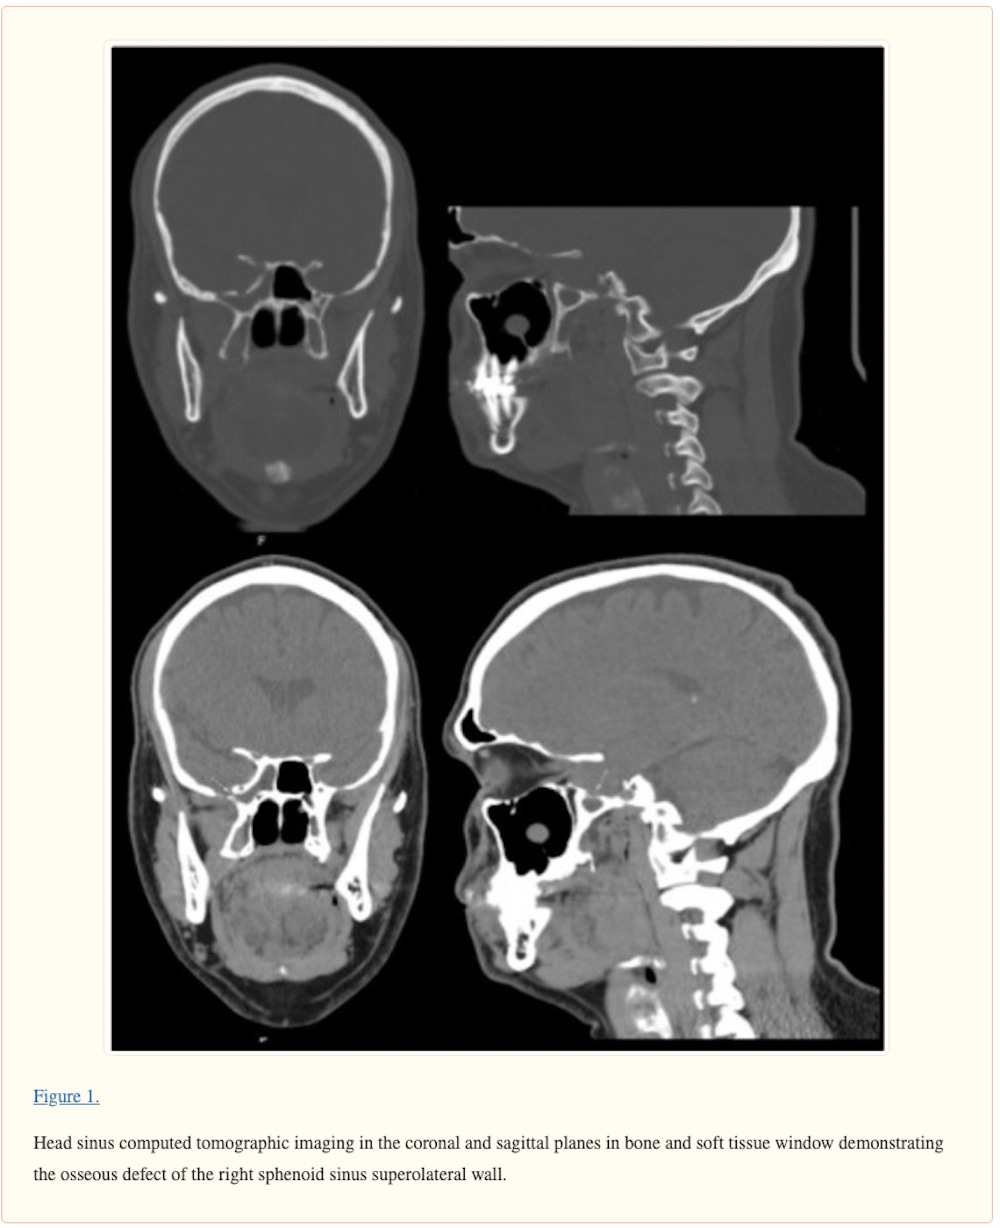

A 40-year-old man presented to the clinic for evaluation of CSF leak following COVID-19 testing via nasopharyngeal swab. During the swab, the patient reported feeling “something crack” upon deeper insertion of the swab and then had a large amount of clear rhinorrhea. Since the COVID-19 test, the patient had persistent clear fluid drain from the right side of his nose when tilting his head forward. The clear fluid was positive for beta-2 transferrin, and head computed tomographic imaging showed a small osseous defect in the superior and lateral wall of the right sphenoid sinus with opacification. The patient had resolution of CSF leak following repair of right skull base defect by an endoscopic transnasal/transsphenoidal approach with nasoseptal flap.